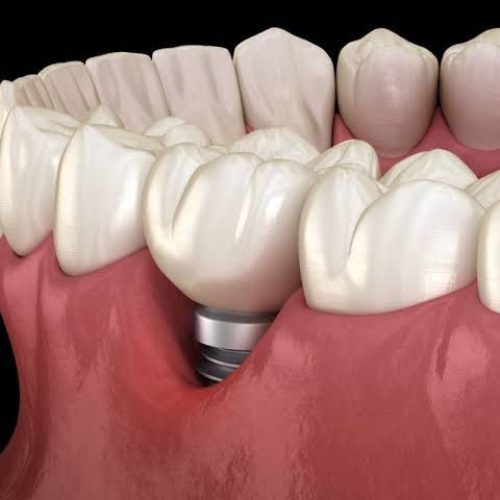

3. Loose Dental Implant:

Osseointegration is the process by which a dental implant fuses with the bone. If this process of osseointegration fails, the implant placed becomes loose and fails. There is nothing you can do about it. Sometimes implants don’t integrate with the bone and even dentists cannot tell you the exact reason.

4. Damage due to excessive force:

Applying excessive force to the dental implant may cause damage to the implant. If the patient is suffering from bruxism (grinding of teeth) that can cause damage to the implant knowingly or unknowingly, which will result in the loosening of the implant and ultimately causing implant failure.

For these patients, night guides are prescribed by the dentist.

Sometimes patients do not wait for 3 months for the healing of Implant and force the dentist to give the prosthesis early. In these cases, early crown or implant might lead to failure.

Sometimes, the patient loose some teeth from the other side and keep on chewing from implant side this excessive force might lead to failure. So, it is better to get your missing teeth replaced